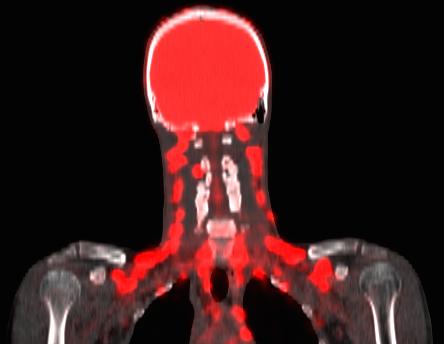

Unlike white fat, which primarily stores energy, brown fat burns energy - often in remarkably large amounts. Sitting just above the collarbone and in the neck, brown fat acts like a heat generator, helping to keep us warm by burning sugar and fat.

The study used a simple and non-invasive technique to measure brown fat activity: a small thermometer placed over the collarbone of participants.

Dr Lee says, "Brown fat sits just under the skin, and it heats up when it's active. So, measuring skin temperature at the collarbone can allow us to estimate brown fat activity.